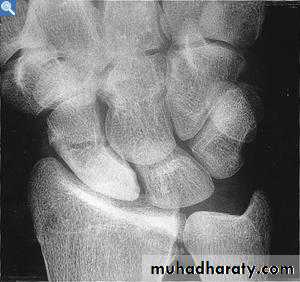

4.In sub capital fracture of the femoral neck & fracture through the waist of the scaphoid bone , the femoral head & proximal pole of the scaphoid become fragmented & dense due to the ischemia .